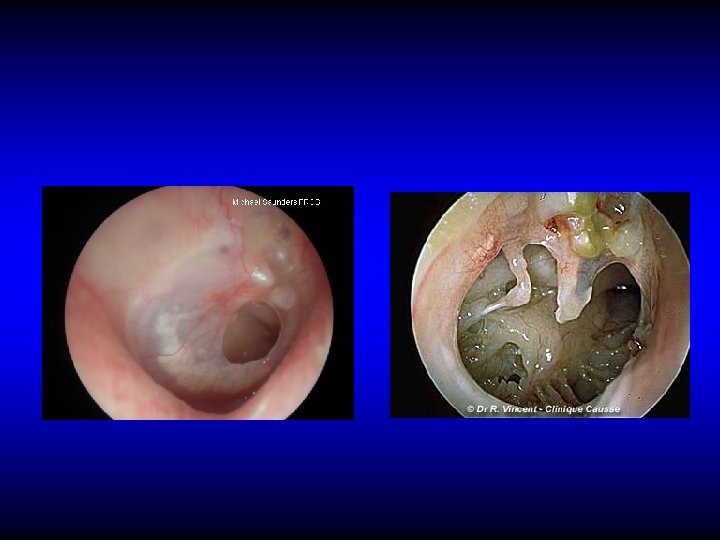

Otoscopic examination • Discharge – Present in TT type if active but may be absent – Usually is present in AA type • Perforation – Central: in TT type – Marginal or attic in AA type with cholesteatoma

Perforation in TT CSOM

Perforation in AA CSOM

Otoscopic examination • Discharge – Present in TT type if active but may be absent – Usually is present in AA type • Perforation – Central: in TT type – Marginal or attic in AA type with cholesteatoma • Polyps, granulation tissue, tympanosclerosis